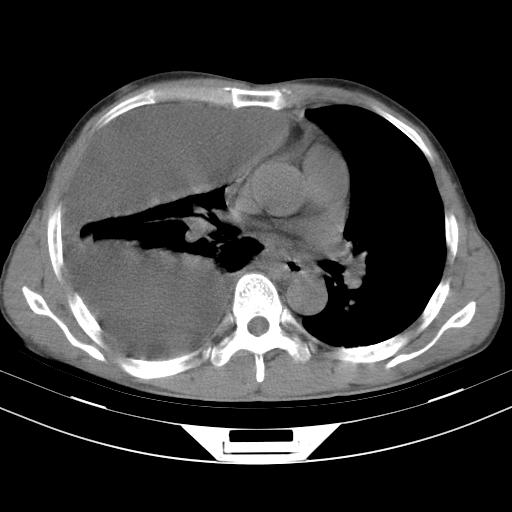

男性,44岁,结核病史多年。现胸闷气短,咳嗽,偶咳血。

右侧胸腔积液

右肺下叶不张

双肺多发结节影最分空洞形成考虑占位不除外结核

1、右侧大量胸腔积液伴右肺压缩性膨胀不全,建议抽液治疗后复查 2、两肺继发性tb伴空洞形成。

1)两肺继发性肺结核伴空洞形成,左肺多发性结核球。2)右侧大量胸腔积液伴右肺部分膨胀不全。3)纵隔淋巴结肿大。